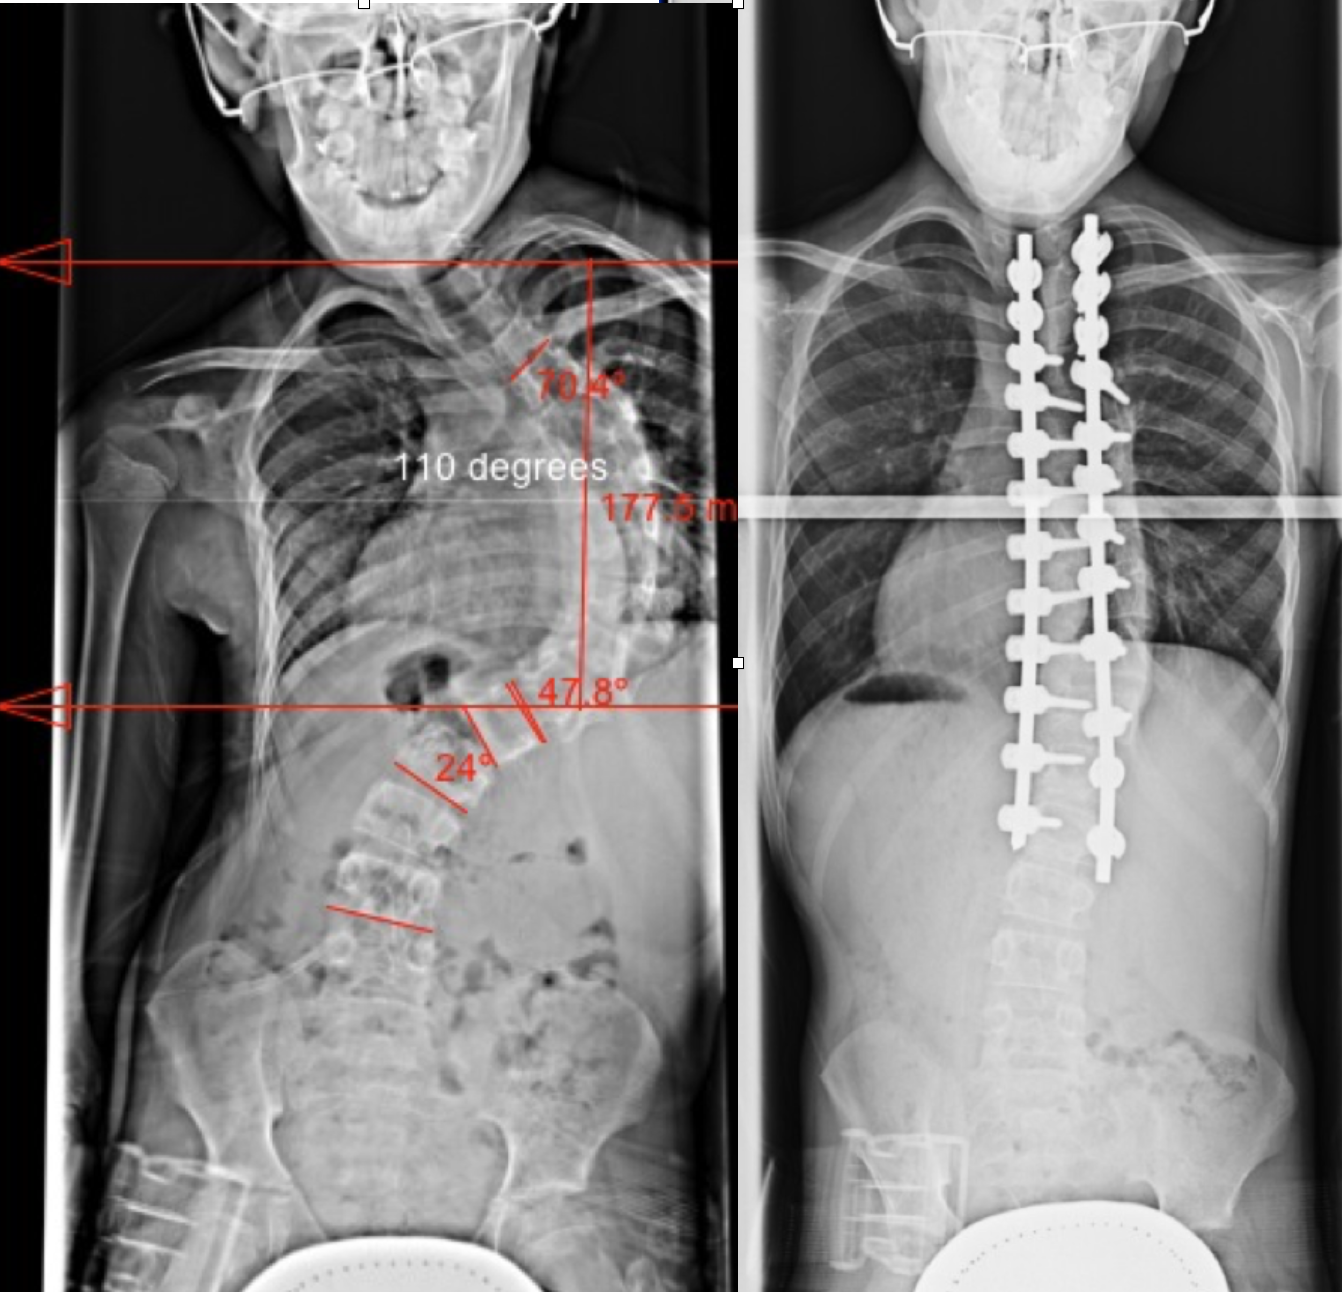

Scoliosis XRay before/after; 28 titanium screws + 2 cobalt chrome rods Scoliosis Titanium Rods Price spinal fusion surgery for scoliosis can reduce the curve of the spine and prevent its progression. The cost of surgery for scoliosis and other types of spinal curvatures depends on. However, there is an alternative, modern. magnet driven rods are now being used for select patients and preliminary results have shown to be able to reduce morbidities, cost,. Scoliosis Titanium Rods Price.